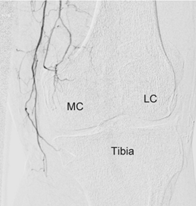

慢性的關節、肌腱、韌帶疼痛,往往伴隨著新生微血管的增生,導致周邊神經敏感度提升而造成長期疼痛;如果能讓這些新生微血管消失,疼痛即可獲得改善。此種治療會在手腕或是鼠蹊部進行局部麻醉,使用極細的導管穿過動脈,找到疼痛部位的新生微血管再注入栓塞的治療藥物,使新生微血管消失、改善疼痛。過程中病人全程清醒,傷口只有針孔大小,術後觀察三十分鐘無不適即可離院;併發症極低,十分安全。治療前的門診評估,會依據每個人不同的疼痛狀況,做詳細的問診、身體及影像學檢查,給患者最好的建議。

膝部退化性關節炎(J Vasc Interv Radiol 2017) 資料來源:中山醫學大學放射科 |

栓塞後